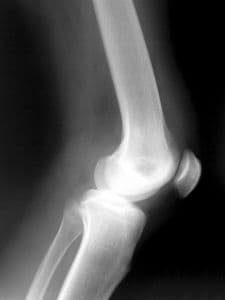

O conceito de reumatismo é longo e engloba 200 tipos de doenças diferentes que atacam o sistema músculo esquelético, ou seja, articulações, músculos, tendões, l...